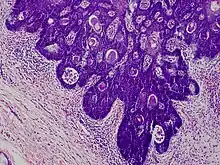

The typical histopathologic features of folliculosebaceous cystic hamartoma lesions are mesenchymal, follicular, and sebaceous elements; these lesions frequently manifest as sebaceous structures that emerge from a core infundibular cyst that is contained inside the dermis.[6] Mesenchymal alterations are frequently observed throughout the stroma and are characterized by fibrillary bundles of collagen with proliferating adipocytes, as well as a rise in capillaries and tiny venules.[7][6] There are clefts separating the neighboring dermis from the epithelial component.[6] In the stroma of lesions, immature adipocytes with lipid droplets and spindle- or starry-shaped nuclei have been observed; these cells are frequently located close to the sebaceous formations.[7]